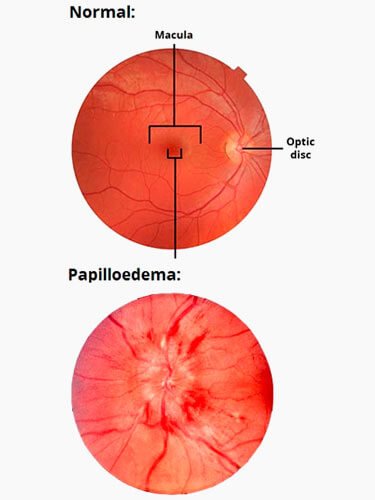

Os sinais e sintomas clínicos incluem cefaléia, zumbido pulsátil, papiledema, obscurecimentos visuais transitórios, perda visual, dor cervical, dorsalgia, e diplopia . Não há evidências de deformidade nem de obstrução do sistema ventricular, e os estudos neurodiagnósticos são normais, exceto pela pressão do líquido cefalorraquidiano (LCR) elevada e pelos sinais dos exames de neuroimagem relacionados( Ressonância Magnética Cerebral , AngioRessonância venosa, Ultrassonografia da bainha nervo óptico). Além disso, não há causa secundária aparente de hipertensão intracraniana.

O diagnóstico normalmente envolve a realização de exames clínicos e fundoscopia, também conhecido como exame de fundo de olho. Nestes testes é possível identificar, por exemplo, a existência de edemas ou demais comprometimentos do nervo óptico.